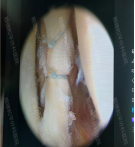

而他们还都有着共同的治疗期望——“最小损伤、最快恢复”的核心诉求,于是骨一区吴建伟主任团队结合两人的病情特点,迅速制定了适配的微创治疗方案。手术均采用“关节镜下膝关节探查清理+半月板修复+取同侧腓骨长肌重建前交叉韧带术”。

仅通过数个5-10毫米的微小切口,借助关节镜的高清视野精准操作,既彻底清理了病变组织、修复了损伤的半月板,又成功重建了前交叉韧带,实现了对关节功能的精准修复。这种微创手术方式不仅创伤小、出血少、术后疼痛轻,更能有效缩短恢复周期,让患者在更短时间内摆脱病痛,回归正常生活与工作。